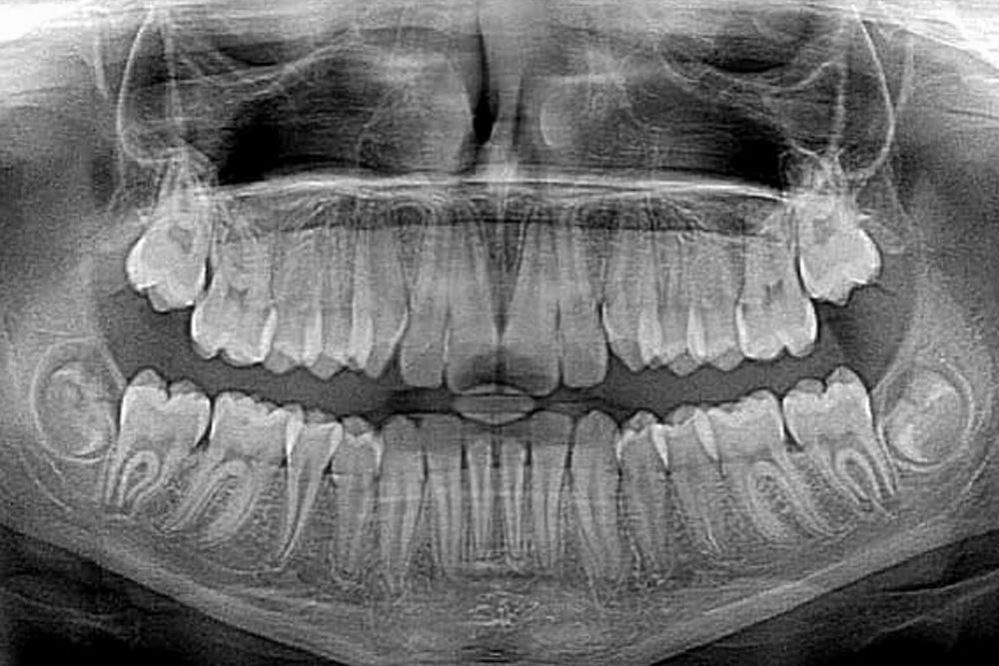

- Детская стоматология – определения положения зачатков постоянных зубов.

- увидеть зачатки постоянных зубов у детей;

- определить строки смены молочных зубов на постоянные;

- Ранняя диагностика аномалий зубочелюстной системы – по мировым стандартам рекомендуется проходить плановую ОПТГ для обнаружения одонтогенных (зубных) кист, пороков развития и опухолей в 10, 15, 20 лет.